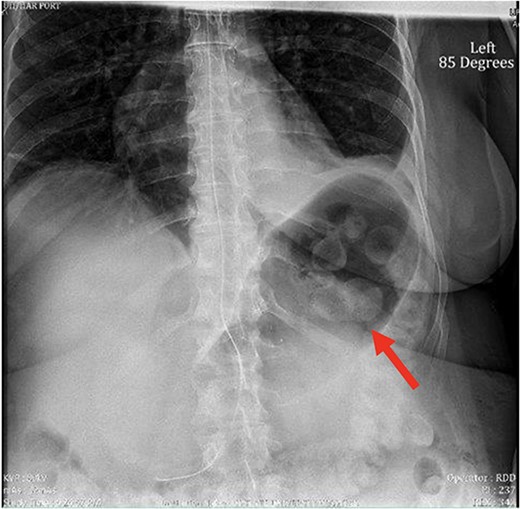

Despite the insertion of the NGT yielding 1500 cc output in 24 hours, the patient continued to experience severe abdominal pain. Urgent abdominal and pelvic computed tomography (CT) scans were taken, as seen in Figs 2–4. The CT scans showed gastric distension and the spleen positioned anteriorly in the right upper quadrant. Consequently, the decision was made to promptly bring the patient to the operating room for a diagnostic laparoscopy with plan to detorse the spleen.

CT of the abdomen and pelvis (axial slice) showing gastric distention and the spleen positioned anteriorly in the right upper quadrant.

Our patient’s pre-existing conditions presented challenges in distinguishing between expected postoperative discomfort and potential complications following her recent adrenalectomy. This uncertainty, combined with a normal WBC count, absence of fever, and regular bowel function, initially led the medical team to attribute her pain to the recent surgery two days prior, delaying her diagnosis and potentially exacerbating her condition. Subsequent imaging became imperative, revealing a persistent large gastric bubble despite NGT decompression, and malposition of the spleen (Fig. 3). This prompted immediate preoperative measures to facilitate a diagnostic laparoscopy.